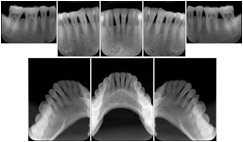

2. A patient requests cosmetic surgery to enhance their facial appearance. The case requires consultation between an orthodontist in New York and an oral surgeon in California. The cephalometric series of 2D projections constructed from a volumetric CT data set that is used for the discussion is arranged by a Structured Display for transfer between the two practitioners.

Cephalometric Series Structured Display

Figure OO-2. Cephalometric Series Structured Display